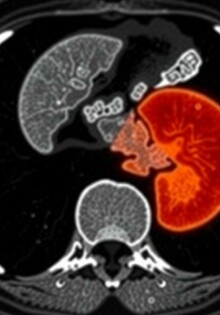

Dolor abdominal derecho: posibles diagnósticos alternativos que debes conocer

Apendicitis y gastroenteritis: cómo diferenciarlas

Diferencia entre apendicitis y diverticulitis: cómo reconocer, diagnosticar y tratar dos causas comunes de dolor abdominal